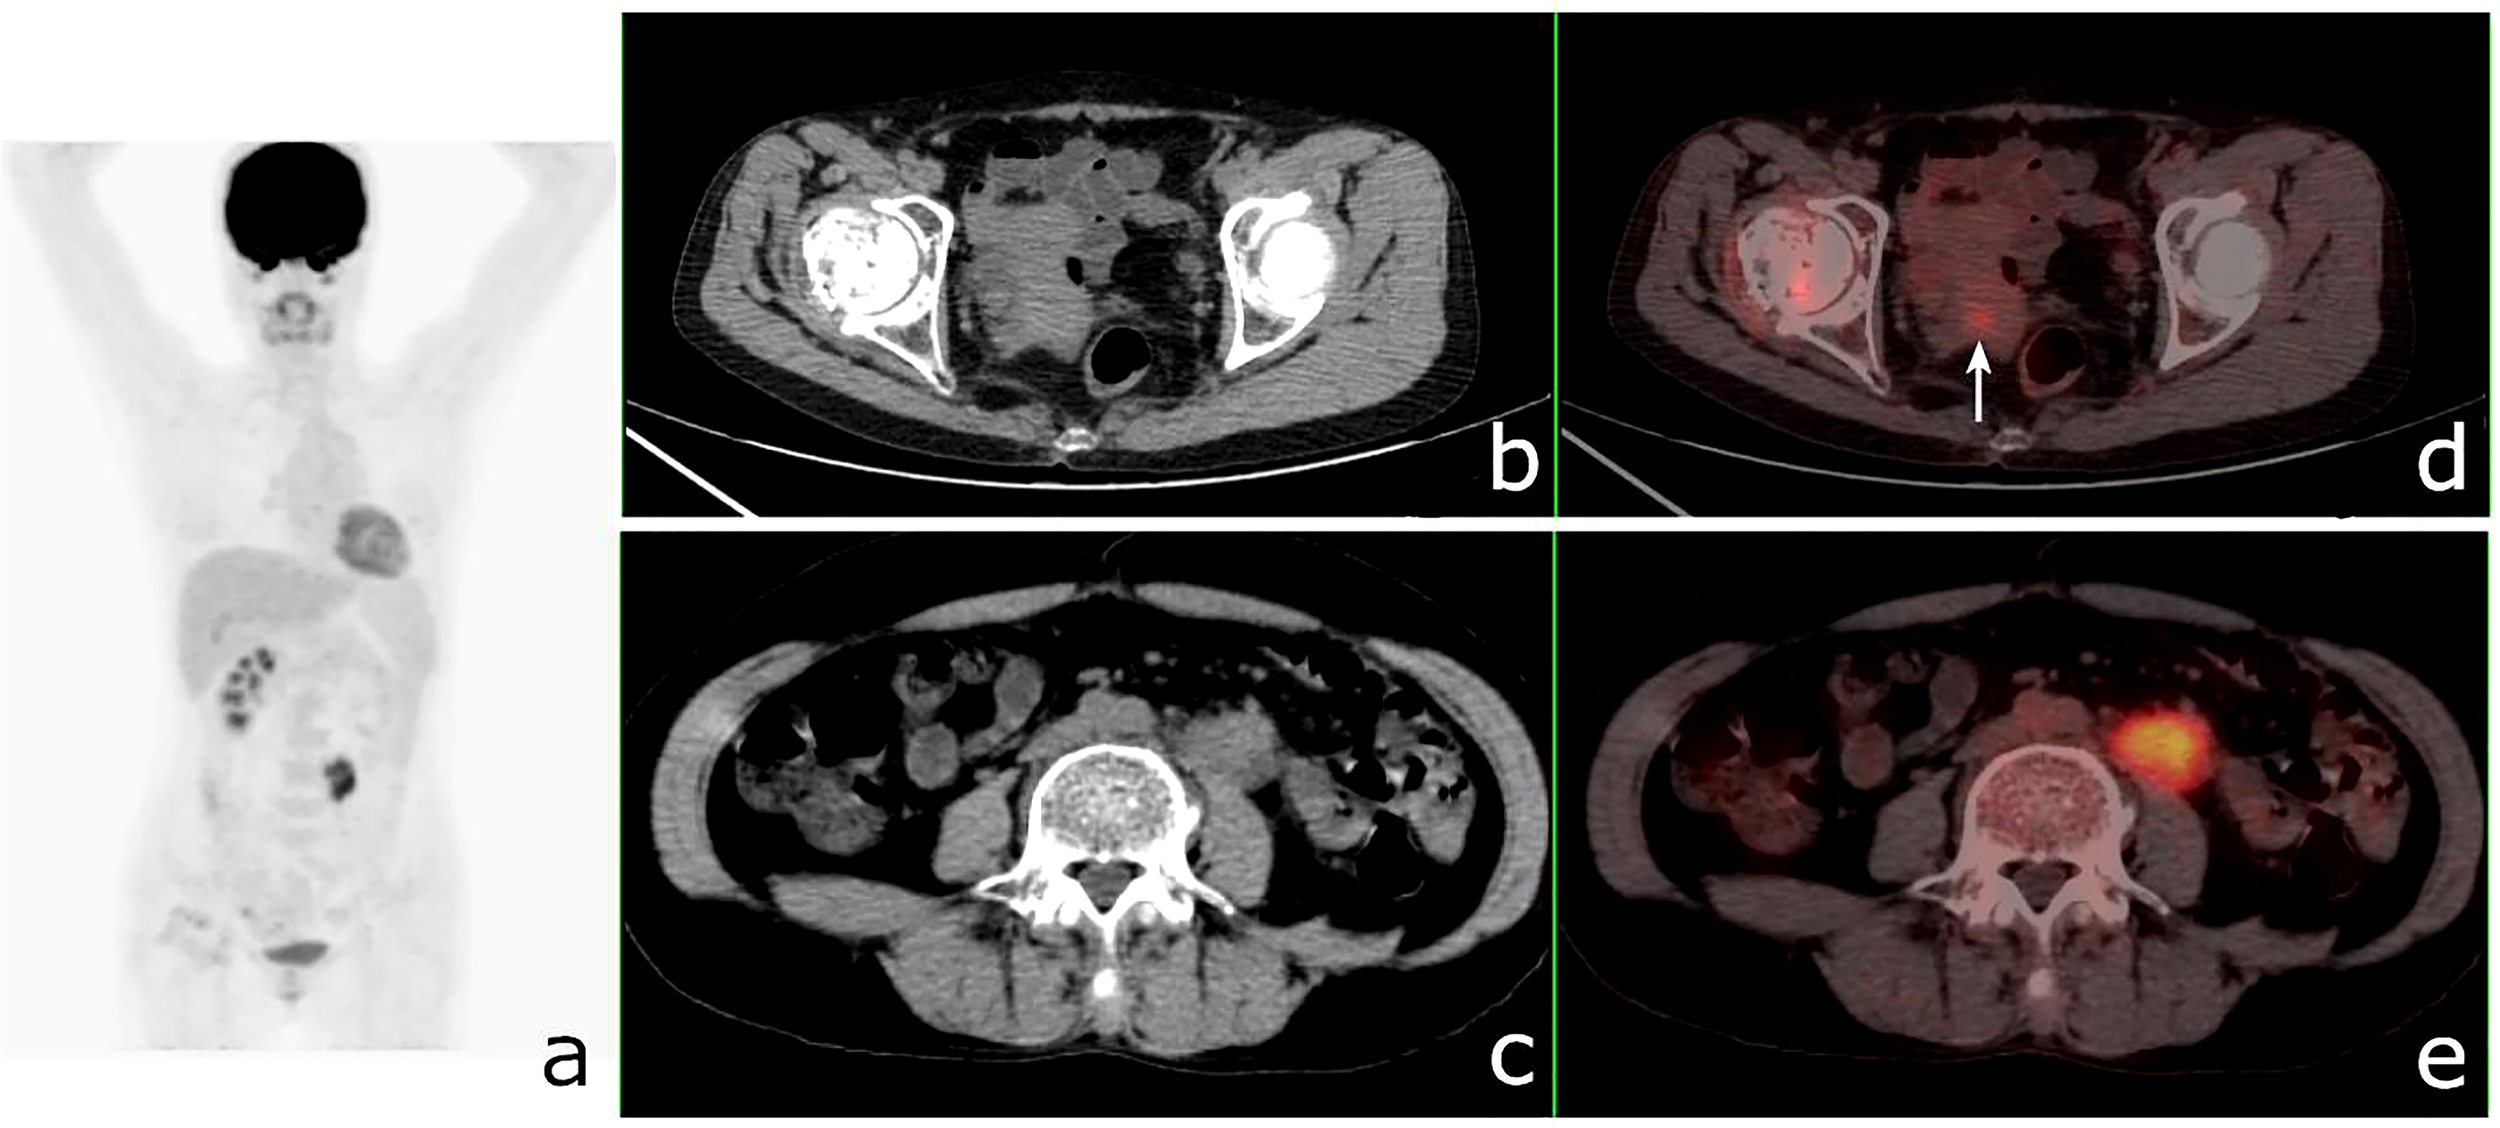

Figure 9 18F-fluorodeoxyglucose positron emission tomography/computed tomography (18F-FDG PET/CT) of a 49-year-old woman with ureteral squamous cell carcinoma and endometrial carcinoma. PET/CT revealed a 41 × 20-mm mass in the left ureter with a maximum standardized uptake value (SUVmax) of 7.7 and a nodular hypermetabolic lesion (SUVmax = 2.7) (arrow) misinterpreted as physiological FDG uptake in the uterine. (A) PET/MIP. (B, C) Axial CT. (C, D) Fusion images.

The therapeutic regimens and the prognosis of SMPMNS patients with or without metastasis were different. In this series, preoperative PET/CT examination improved the diagnostic accuracy and changed the treatments for some patients. Comparison of the survival times of SMPMNS patients with and without documented metastases showed a significant difference in the overall survival rates between these two categories. In this series, more than one-third of the cases showed suspected metastases on 18F-FDG PET/CT, and the patient-based diagnostic accuracy of 18F-FDG PET/CT and CI for metastases was not significantly different; nevertheless, 18F-FDG PET/CT had higher sensitivity, as it detected more unexpected metastatic lesions that were missed or not imaged on CI. However, 18F-FDG PET/CT had lower specificity, as it overestimated the number of metastatic lesions in some cases of SMPMNS, particularly the number of metastatic lymph nodes. Similar findings have been observed in the 18F-FDG PET/CT assessments of patients with other malignancies (26). Increasing the SUVmax threshold for the diagnosis of lymph node metastasis may improve the diagnostic accuracy (27).

To our knowledge, there are only a few studies evaluating the diagnostic performance of 18F-FDG PET/CT for SMPMNS. In this series, SMPMNS were considered in 28 cases, and most of the primary lesions (including diagnosed and misdiagnosed) have been revealed on 18F-FDG PET/CT imaging. We noted one primary tumor of SMPMNS that was more frequently missed on CI primarily due to the regional imaging modalities and the general lack of awareness regarding SMPMNS on the part of clinicians, with their attention tending to be focused on the identified primary lesion. 18F-FDG PET/CT, which can more comprehensively reveal lesions due to its whole body surveillance, will help in increasing clinicians’ awareness regarding SMPMNS. Additionally, one primary tumor of SMPMNS was easily mistaken for metastasis, especially in patients with metastases, which will more likely lead to confusion in the diagnosis. 18F-FDG PET/CT, which allows combining metabolic information with anatomic details, reduces the incidences of misdiagnosis, i.e., tumors with different clonal origins that were generally believed to have a different biological behavior, leading to different uptakes of FDG. Misinterpretation of a high FDG uptake in lesions as physiological uptake on PET/CT is also an important reason for the missed diagnosis (Figures 8, 9).